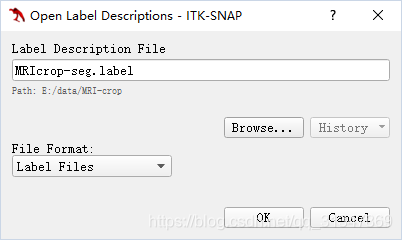

下载标签

额外导入标签文件:Segmentation -> Import Label Descriptions

Browse 选择标签文件:

需要创建自己的 label,只需要在 label editor 中改变已存在的 label 或新建 label

保存自己的 label 设置,选择导出即可